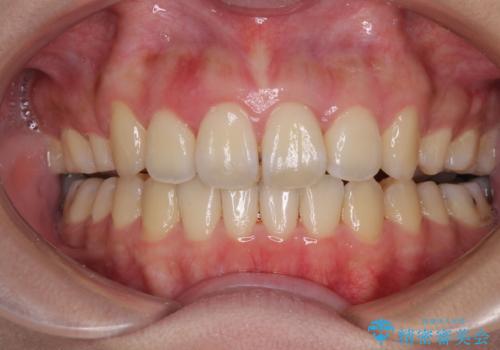

- 八重歯と叢生を気にして来院された患者様です。

上下の前歯が非接触であり、叢生や八重歯が顕著であったため、上顎左右第一小臼歯2本を抜歯して排列することとしました。

抜歯により移動量が多くなるため、ワイヤーや補助装置を活用し、その後インビザラインによる矯正治療を行うこととしました。